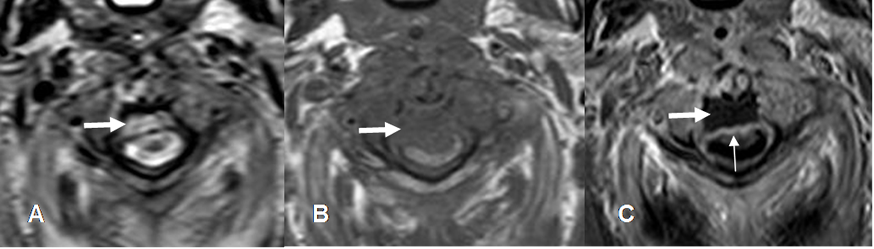

Fig 143 D. Absceso epidural.

A: RM axial en T2, B: RM axial en T1 y C: RM axial en T1 con contraste. Igual paciente anterior. Colección epidural que comprime la parte anterior del saco, hiperintensa en T2, hipointensa en T1 y con realce posterior de las meninges, por empiema. (Flecha delgada).